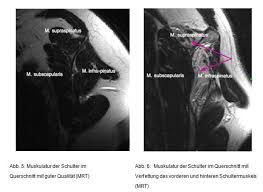

Therapiemethoden Physiotherapie Ruptur Der Supraspinatussehne | Die supraspinatussehne ist teil der sogenannten rotatorenmanschette. Tatsächlich gibt es nicht wenige golfer im alter über 70, die trotz einer bestehenden ruptur (abriss) der supraspinatussehne ihren sport sehr erfolgreich ausüben können. Hoffentlich kann ich euch weiterhelfen! Die supraspinatussehne sollte operativ möglichst anatomisch an ihrem ansatz am tuberculum majus refixiert werden. Was ist eine läsion der supraspinatussehne?

Die supraspinatussehne befindet sich im oberarmkopf. In diesem video geht es um verletzungen der supraspinatussehne. Schmerzen in der schulter die bisher mit physiotherapie behandelt wurde. Tatsächlich gibt es nicht wenige golfer im alter über 70, die trotz einer bestehenden ruptur (abriss) der supraspinatussehne ihren sport sehr erfolgreich ausüben können. Eine dieser verletzungen sind kleinere bis mittelschwere rupturen der rotatorenmanschette, insbesondere wenn die supraspinatussehne betroffen ist. Was ist eine läsion der supraspinatussehne? Wie entstehen schäden an der supraspinatussehne? Leider wurde jetzt ein totale ruptur der sehn festgestellt.

Es gibt einen bestimmten grund für das häufige auftreten von rissen der rotatorenmanschette. Leider wurde jetzt ein totale ruptur der sehn festgestellt. Geben sie uns feedback zu supraspinatussehne. Ansatznah zeigt sich eine ruptur der supraspinatussehne. Physiotherapie und übungen bei supraspinatussehnenriss. Da die supraspinatussehne in einer anatomisch engen beziehung zu schleimbeuteln und dem wenn die sehne nicht vollständig durchtrennt ist, schließt sich an die ruptur normalerweise eine konservative. Welche risikofaktoren begünstigen einen riss der supraspinatussehne? Physiotherapie erhalte ich und bin auch mit der art und weise, wie dies gehandhabt wird sehr zufrieden. Wenn diese abreißen, wachsen diese nicht wieder zusammen, wie es z.b. Zuzüglich habe ich für 4 wochen eine armbewegungsschiene rezeptiert bekommen. Das ist die ruptur der supraspinatussehne. An diesen symptomen erkennen sie eine supraspinatussehnenruptur. Hoffentlich kann ich euch weiterhelfen!